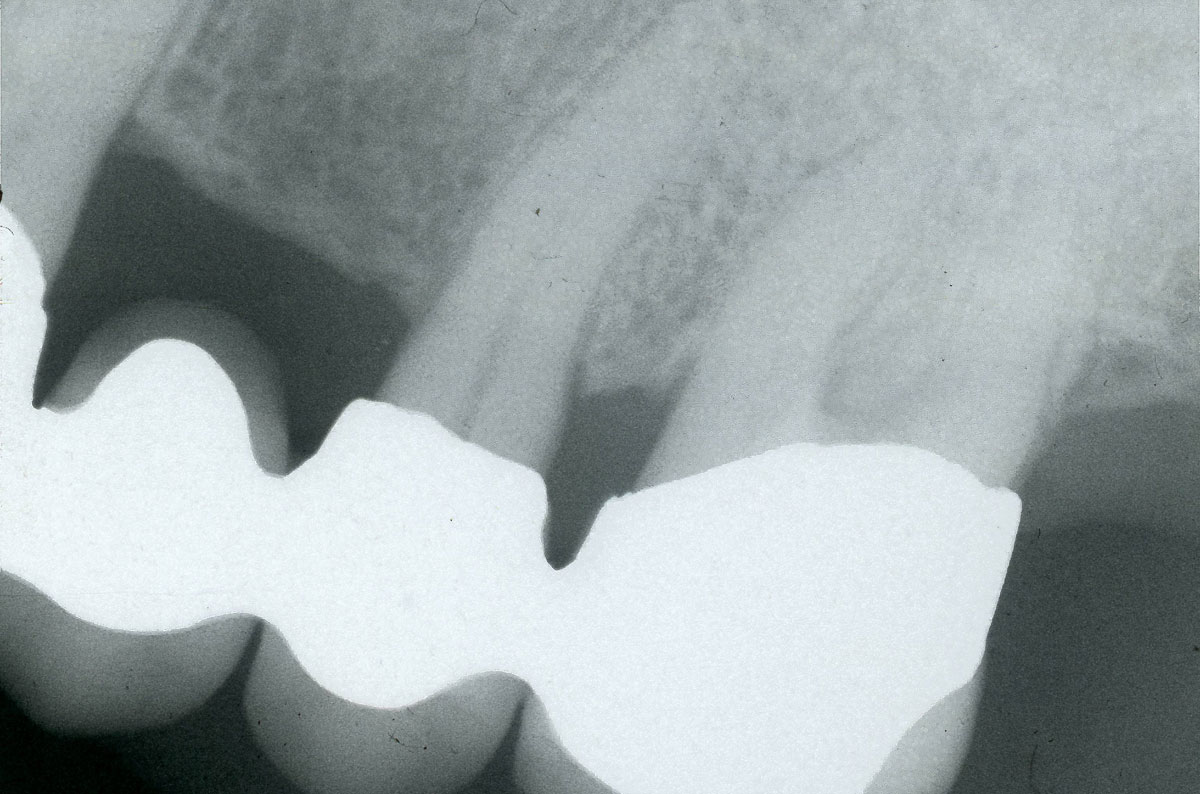

Пример ампутации (этот мост был во рту 25 лет)

При ампутации корня зубная коронка сохраняется. После пломбирования корня мы удаляем поражённый корень. Также и здесь на зуб надо одеть коронку.